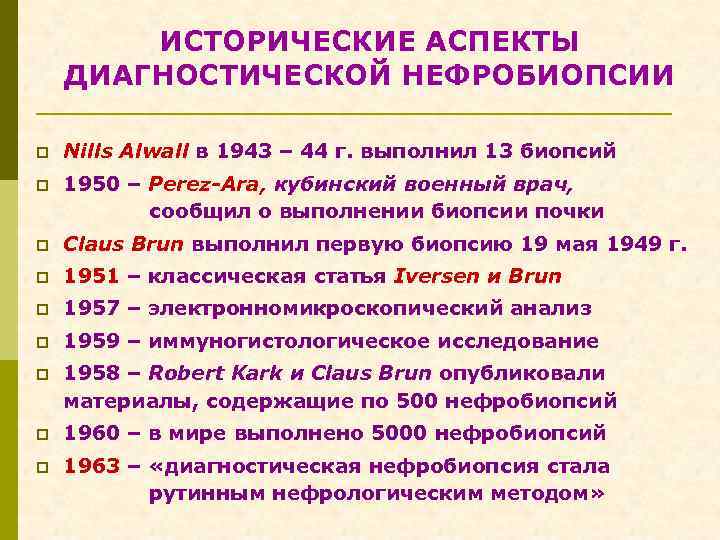

ИСТОРИЧЕСКИЕ АСПЕКТЫ ДИАГНОСТИЧЕСКОЙ НЕФРОБИОПСИИ p Nills Alwall в 1943 – 44 г. выполнил 13 биопсий p 1950 – Perez-Ara, кубинский военный врач, сообщил о выполнении биопсии почки p Claus Brun выполнил первую биопсию 19 мая 1949 г. p 1951 – классическая статья Iversen и Brun p 1957 – электронномикроскопический анализ p 1959 – иммуногистологическое исследование p 1958 – Robert Kark и Сlaus Brun опубликовали материалы, содержащие по 500 нефробиопсий p 1960 – в мире выполнено 5000 нефробиопсий p 1963 – «диагностическая нефробиопсия стала рутинным нефрологическим методом»

ИСТОРИЧЕСКИЕ АСПЕКТЫ ДИАГНОСТИЧЕСКОЙ НЕФРОБИОПСИИ p Nills Alwall в 1943 – 44 г. выполнил 13 биопсий p 1950 – Perez-Ara, кубинский военный врач, сообщил о выполнении биопсии почки p Claus Brun выполнил первую биопсию 19 мая 1949 г. p 1951 – классическая статья Iversen и Brun p 1957 – электронномикроскопический анализ p 1959 – иммуногистологическое исследование p 1958 – Robert Kark и Сlaus Brun опубликовали материалы, содержащие по 500 нефробиопсий p 1960 – в мире выполнено 5000 нефробиопсий p 1963 – «диагностическая нефробиопсия стала рутинным нефрологическим методом»